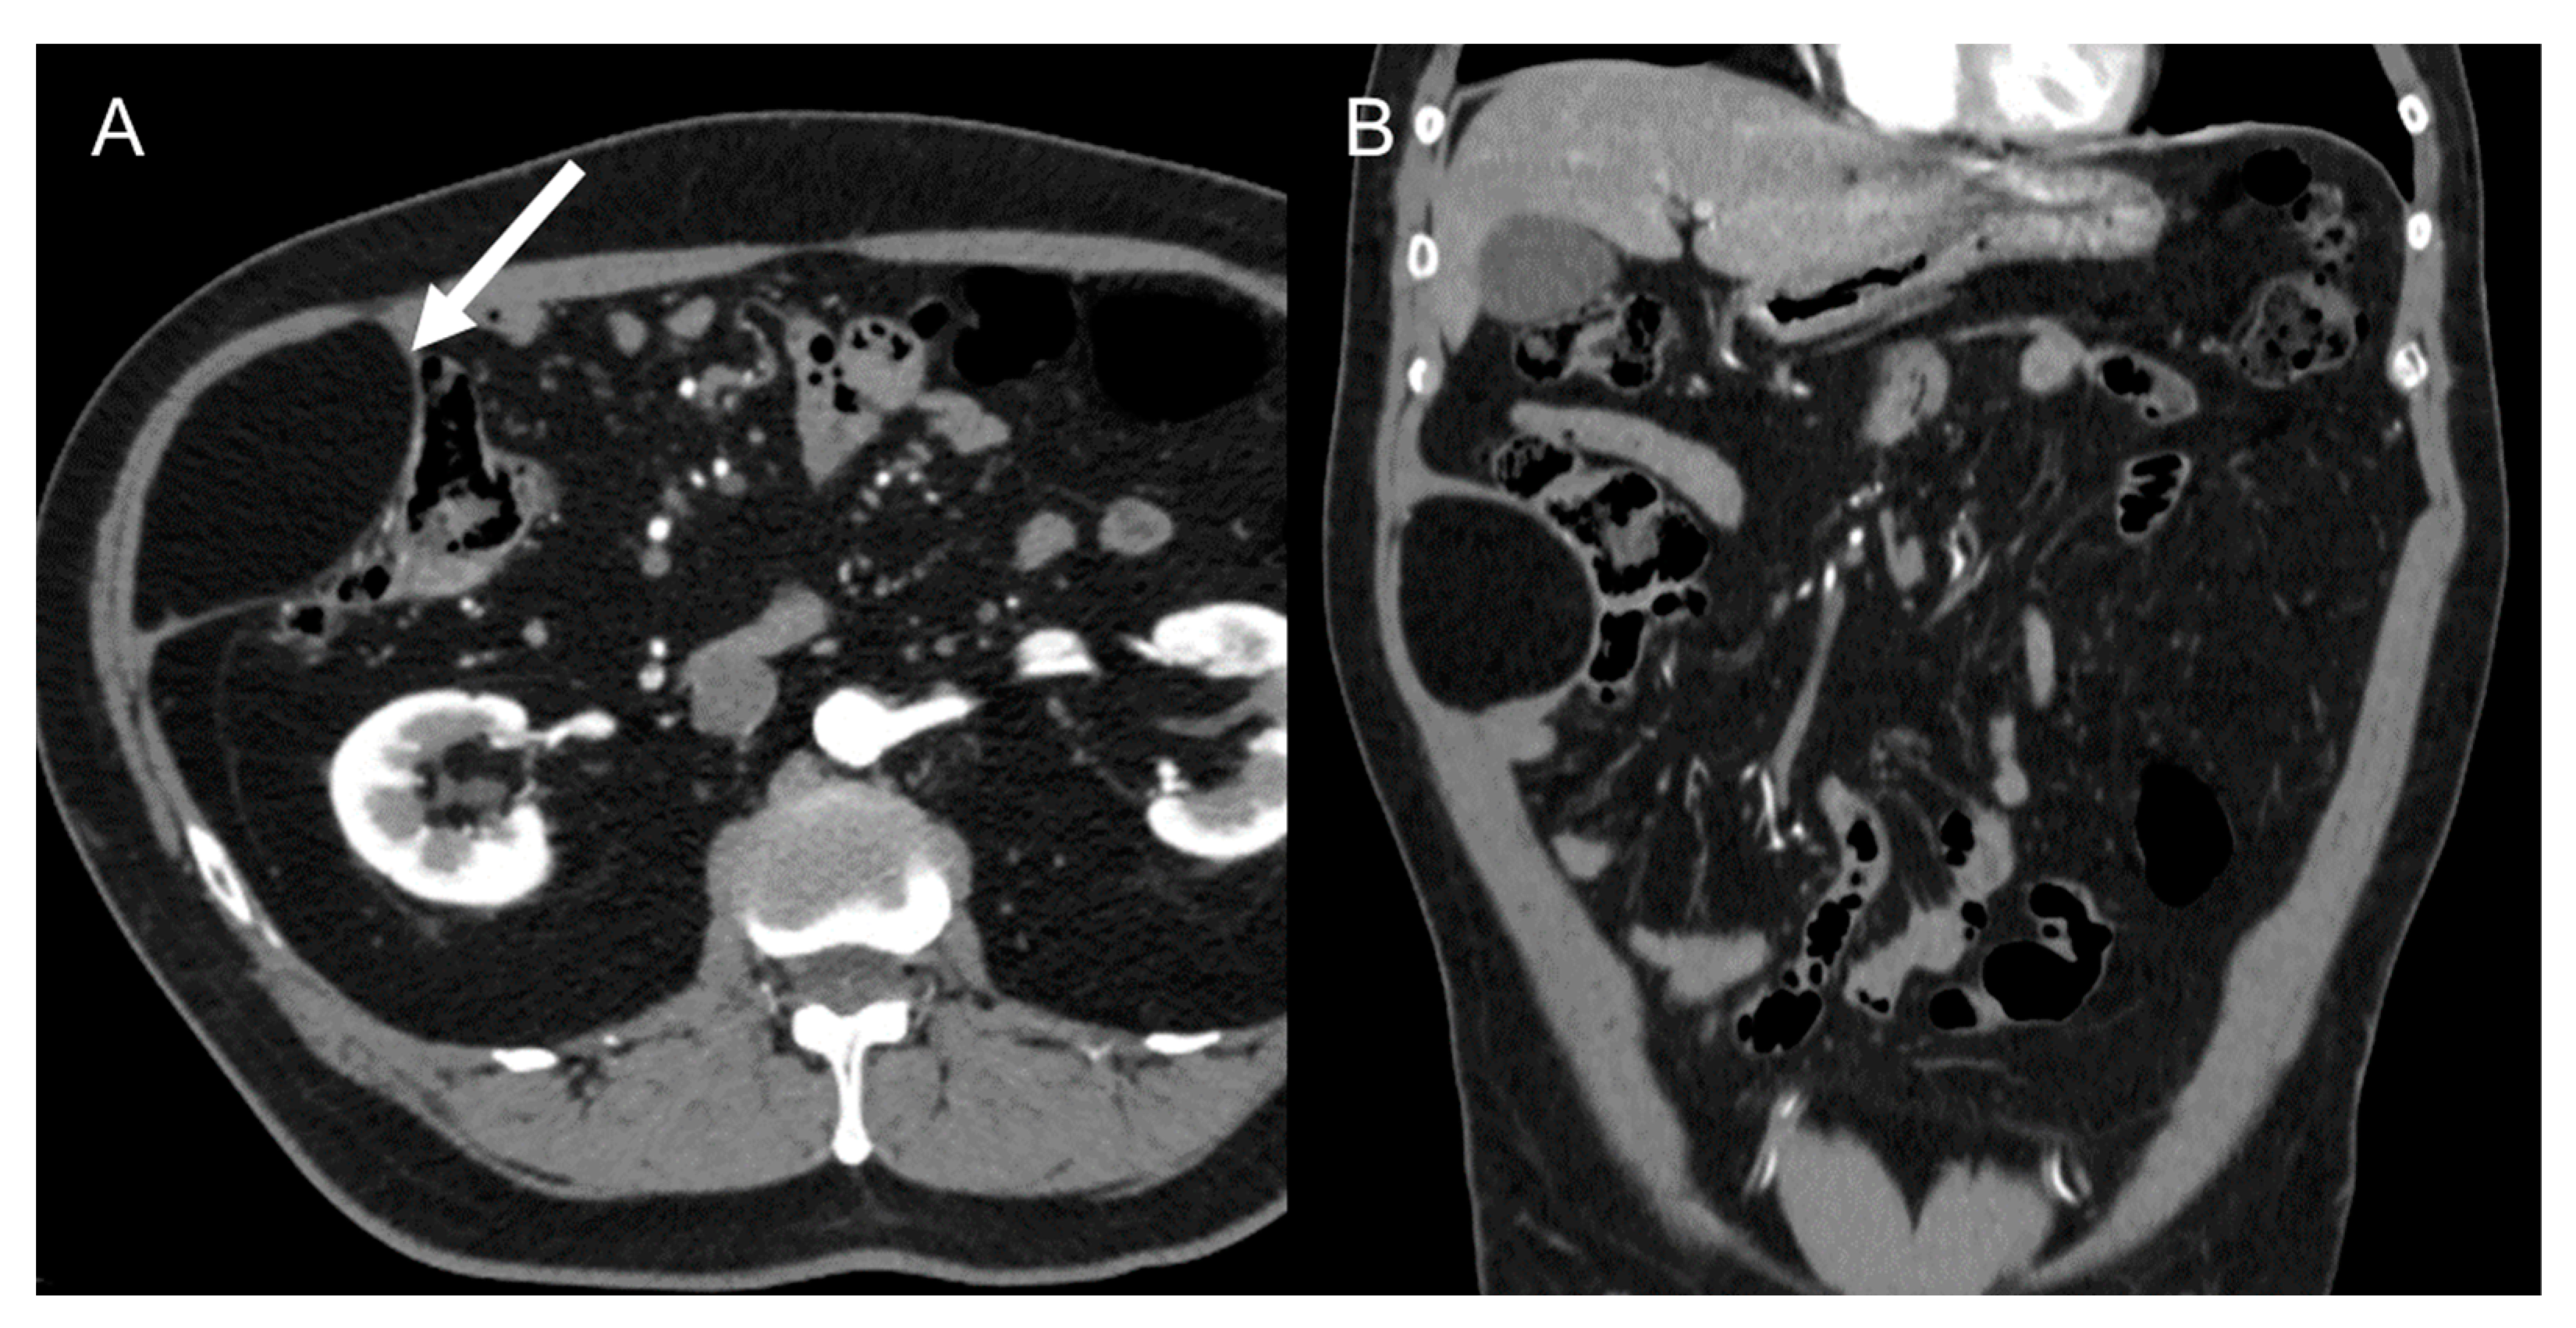

3.3. Solitary Fibrous Tumors (SFT)

Although their imaging appearance is nonspecific, most solitary fibrous tumors (Figure 5) show heterogeneity and are highly vascular, with prominent collateral vessels [38,44,45]. These tumors are well defined, with intense delayed contrast enhancement due to the fibrous stroma [40]. SFT may rarely exhibit cystic degeneration, necrosis, and calcifications [44]. MRI signal intensity is variable and dependent on cellularity and the abundance of myxoid stroma and/or fibrous tissue [40]. Solitary fibrous tumors are typically hypo-to-isointense to muscle on T1-weighted MRI and hypointense on T2-weighted sequences [45]. Flow voids may be present because of prominent intralesional vessels [45,46].

Figure 5.

Solitary fibrous tumor in 76-year-old man. Axial CT on venous phase shows a 5 cm well-defined solid mass with heterogeneous enhancement (arrow). The lesion was histologically confirmed at biopsy.